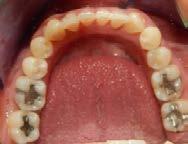

En los estudios intraorales de inicio en las fotografías se muestra en la de frente el diastema anterior, con la línea media dental superior e inferior no coincidentes, la mordida profun da anterior (Figura 2), en la lateral derecha clase l molar y canina bila teral (Figura 3), el apiñamiento leve superior e inferior y la forma de las arcadas.

Figura 1. Extraoral de inicio de frente. Figura 2. Intraoral de frente derecha, izquierda. Figura 3. Oclusal superior e inferior arcadas cuadrada. Figura 4. Radiografía lateral de cráneo. Figura 5. Rx Panorámica.